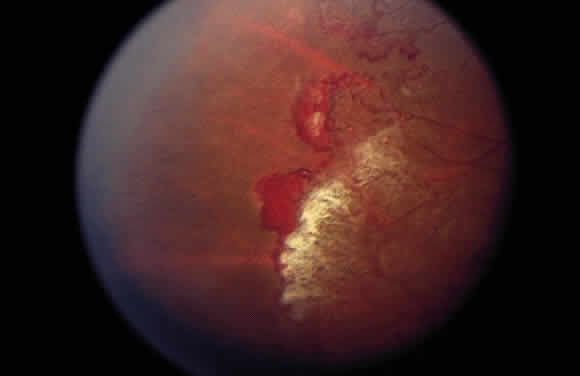

A varying degree of peripheral retinal nonperfusion is present in all patients with this disease. The nonperfusion generally is confluent and sharply demarcated from the posterior perfused retina (Fig. 3). Fine white lines representing the remains of obliterated large vessels (ghost vessels) often are seen in the area of nonperfusion. The temporal retina is most commonly affected.

Elliot and Spitnas and colleagues have documented the abnormalities at the junction between the anteroperipheral nonperfused and the posterior perfused retina.9,10 Intraretinal hemorrhages often first appear in the affected area, followed by an increase in vascular tortuosity with frequent collateral formation around occluded vessels (see Fig. 3). Microaneurysms, arteriovenous shunts, and venous beading are commonly seen at the junction (Fig. 4). Fluorescein angiography enhances these abnormalities and often demonstrates staining at the stumps of obliterated vessels.